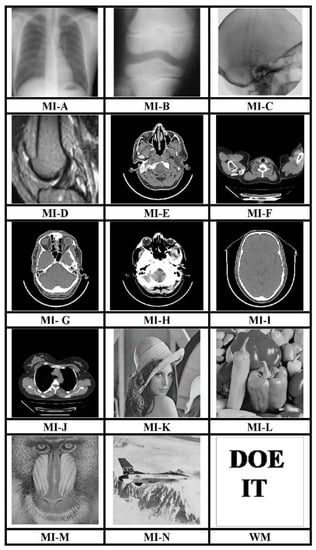

The MATLAB R2017a platform has been utilized for carrying out the experimental investigations for different gray-scale natural and MI. Both types of images that have been used for testing have dimensions 512 × 512. We have conducted experiments using a 64-bit Windows 10 Operating system with an i5 processor, 8 GB RAM, and 2.40 GHz clock speed. The different images, as well as a logo as WM, have been represented in Figure 3. The binary WM employed for authentication purposes has a 128 × 128 size. The technique is evaluated for a payload of 196,608 bits or 0.75 bits per pixel (bpp). The scheme reports an average encryption speed close to 1Mbps. The image quality metrics applied for evaluation of the scheme include normalized cross-correlation (NCC), peak signal to noise Ratio (PSNR), and structural similarity measure index (SSIM) [16,17,18,19,20]. In-depth analysis has been performed, which includes imperceptibility analysis, computational complexity analysis, and fragility analysis. Furthermore, a detailed comparison of many contemporary techniques has been described. Furthermore, the fragility analysis carried out reveals that the WM is fragile to all possible attacks and can easily detect tampering of data.

Figure 3.

512 × 512 test images and 128 × 128 binary WM.